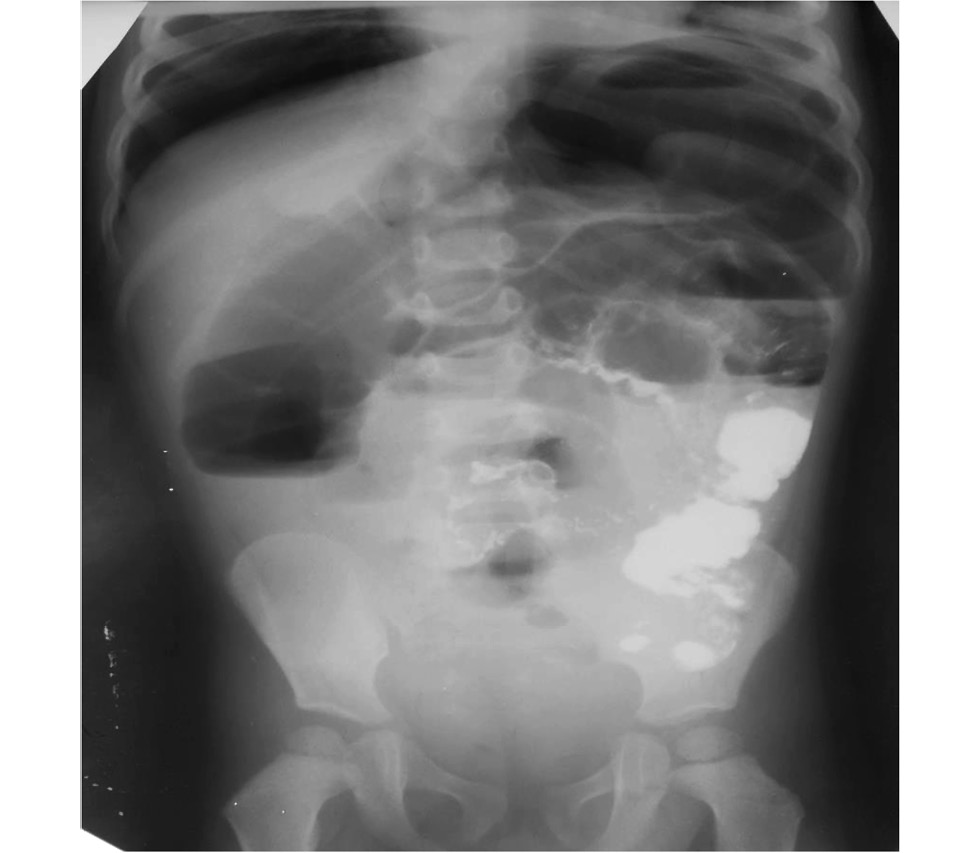

Обзорная рентгенограмма органов брюшной полости: выявлены неравномерное наполнение кишечника, растянутые газом петли кишечника, чаши Клойбера и свободный газ под куполом диафрагмы не выявлены (рис. 1).

Рис.1. Обзорная рентгенография брюшной полости: перерастянутые петли кишечника.

Fig. 1. Overview radiography of the abdominal cavity: overgrown intestinal loops.